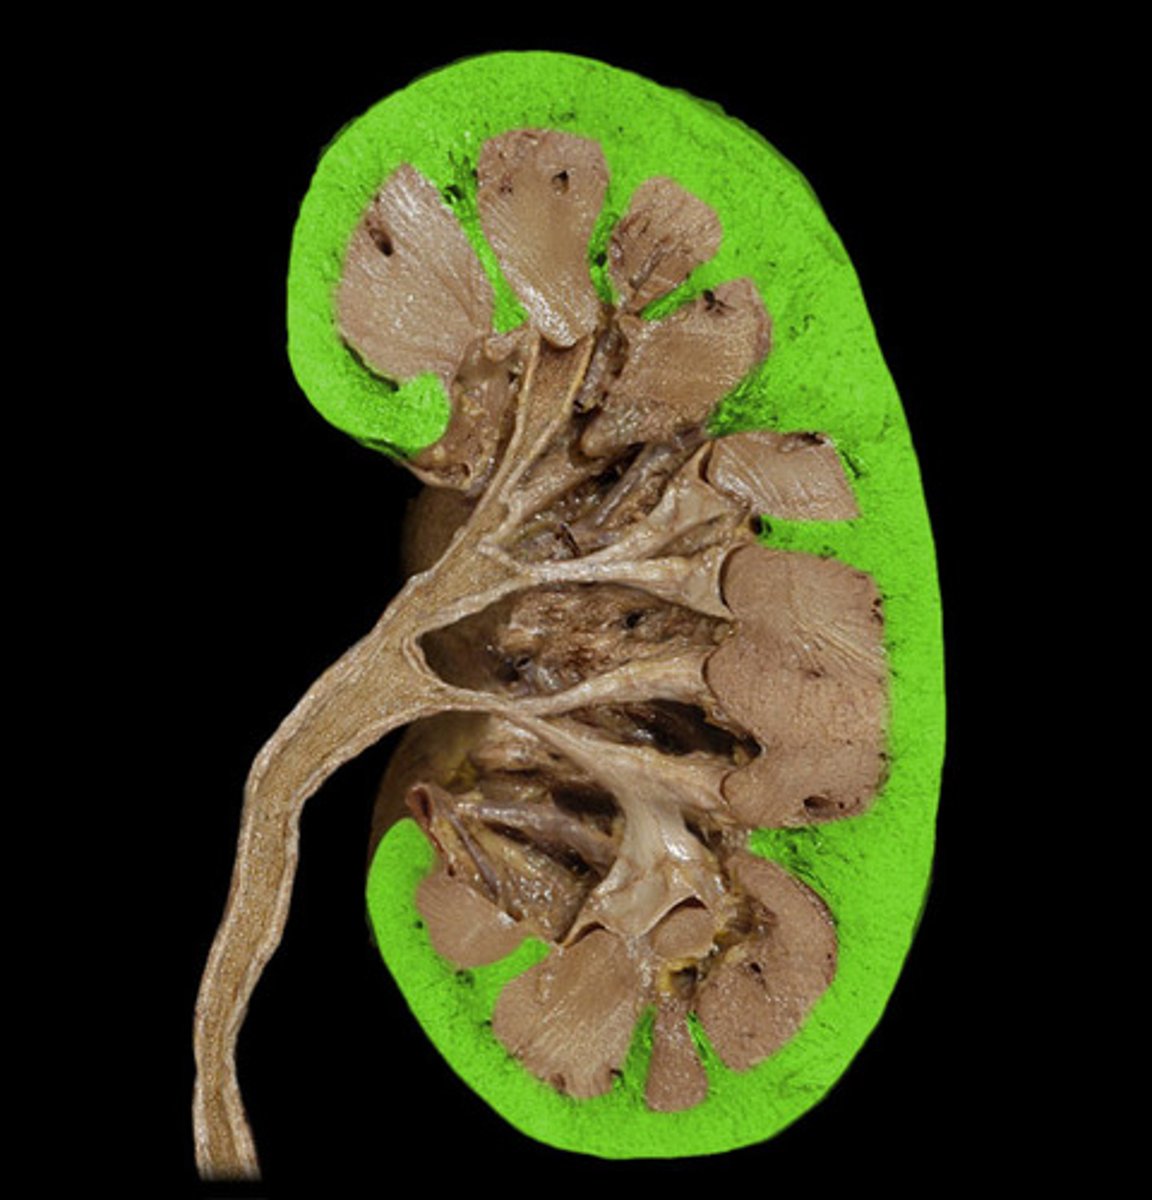

Renal capsule

What is this?

Renal cortex